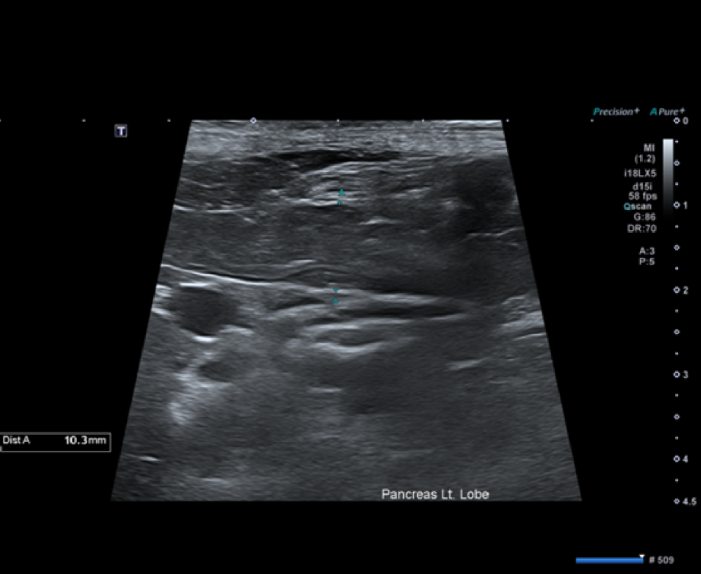

또한 복부 초음파 재검사에서 이전에 관찰되던 췌장 주변 지방의 고에코성 변화와 부종 소견이 개선되는 것으로 확인되었습니다.